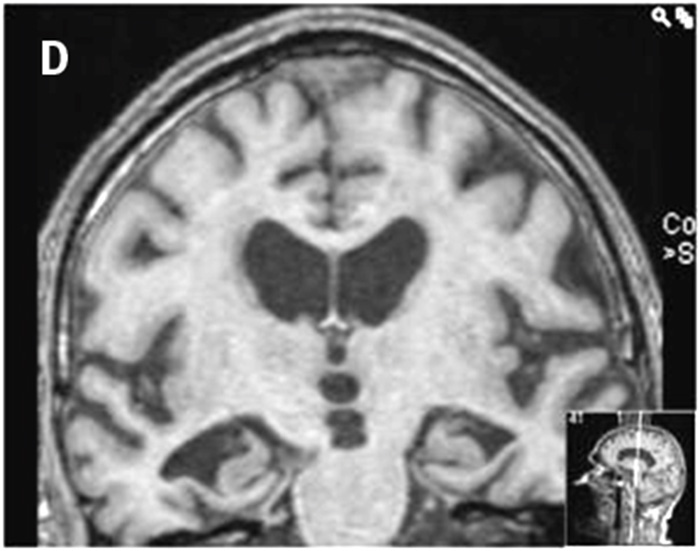

Bedömningen sker enligt en femgradig skala, 0–4, där MTA 0 och MTA 1 visar normala förhållanden och MTA 2–4 ökande grad av atrofi. MTA 2 är patologiskt hos patienter yngre än 70 år och MTA 3 är patologiskt hos alla patienter under 80 år, medan MTA 4 alltid måste uppfattas som patologiskt oavsett patientens ålder (Figur 1) [15].

Metoden togs ursprungligen fram för bedömning av MR-bilder men kan även användas för bedömning av medial temporallobsatrofi med dagens DT-teknik och för jämförelse mellan MRT och DT [16] (Figur 2). Resultat från denna metod har visats vara signifikant korrelerade med manuella mätningar av hippocampus [15], och sensitiviteten och specificiteten är jämförbara med automatiska metoder för volymberäkningar och mätning av kortikal tjocklek [17]. När det gäller reliabilitet (intra- och inter-) över tid är den mycket hög för en erfaren bedömare. Dock är reliabiliteten något lägre mellan två bedömare om de inte arbetar tillsammans. Den är också starkt beroende av erfarenhet hos bedömaren [18].

Figur 1. MTA-graderna 0 (A), 1 (B), 2 (C), 3 (D) och 4 (E).

Figur 2. MR från år 2009 (A) och DT från år 2012 (B) på samma patient med diagnosen Alzheimers sjukdom. Notera progress av såväl medial temporallobsatrofi som ventrikeldilatation.